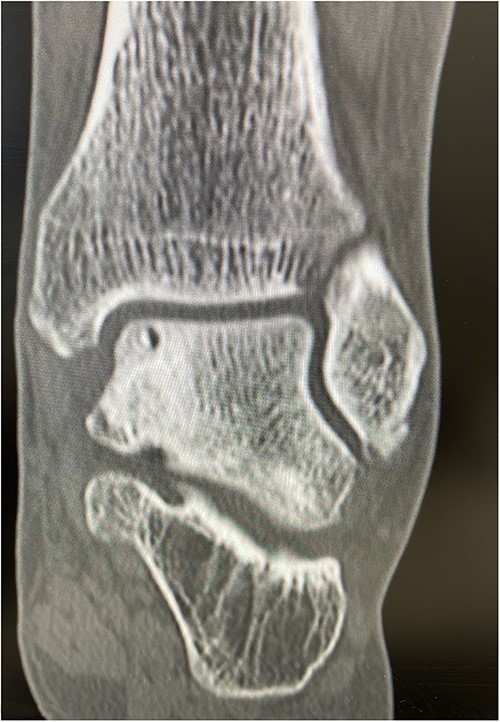

He presented with no relevant medical history and worked as a chemical plant supervisor, which required continuous movement throughout the day. Clinical examination revealed deep-seated pain around the medial aspect of the ankle with an intact range of motion and ankle alignment. His MOXFQ score was 48/80. CT scan revealed a large but well-contained, subchondral cyst in the medial talus of the ankle (Fig. 4).